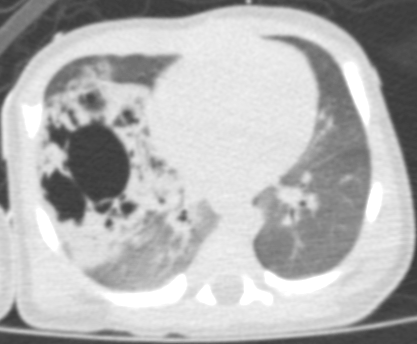

Una radiografia del torace documenta un campo polmonare di destra in gran parte occupato da opacit� disomogenea, nel cui contesto si evidenziano multiple areole di radio-trasparenza; campo sinistro senza alterazioni e lieve sbandieramento del mediastino (Figura 1). Il quadro appare compatibile con la diagnosi prenatale di CCAM. Visto il rapido miglioramento clinico del quadro respiratorio e la normalit� dell'emogas-analisi, la N-CPAP viene rimossa dopo poche ore. | Figura 1. Rx-torace: campo polmonare di dx in gran parte occupato da opacit� disomogenea: si

evidenziano multiple areole di radio-trasparenza; campo sx senza

alterazioni e lieve sbandieramento del mediastino. L'esame

evidenzia un catetere ombelicale che si proietta in sede atriale

(ritirato subito dopo). In sede epigastrica un area circolare di

radiotrasparenza, attribuibile a un elemento dell'incubatore. Per una miglior definizione del problema, anche in vista dell'intervento, viene effettuata una TC-polmonare che evidenzia a destra una formazione irregolarmente ovalare di circa 5 cm di diametro massimo, apparentemente ben marginata, con numerose formazioni cistiche aerate circostanti (Figure 2 e Figura 3). Alla luce della diagnosi il bambino viene quindi sottoposto con successo ad intervento di lobectomia parziale dei lobi medio e superiore di destra. |